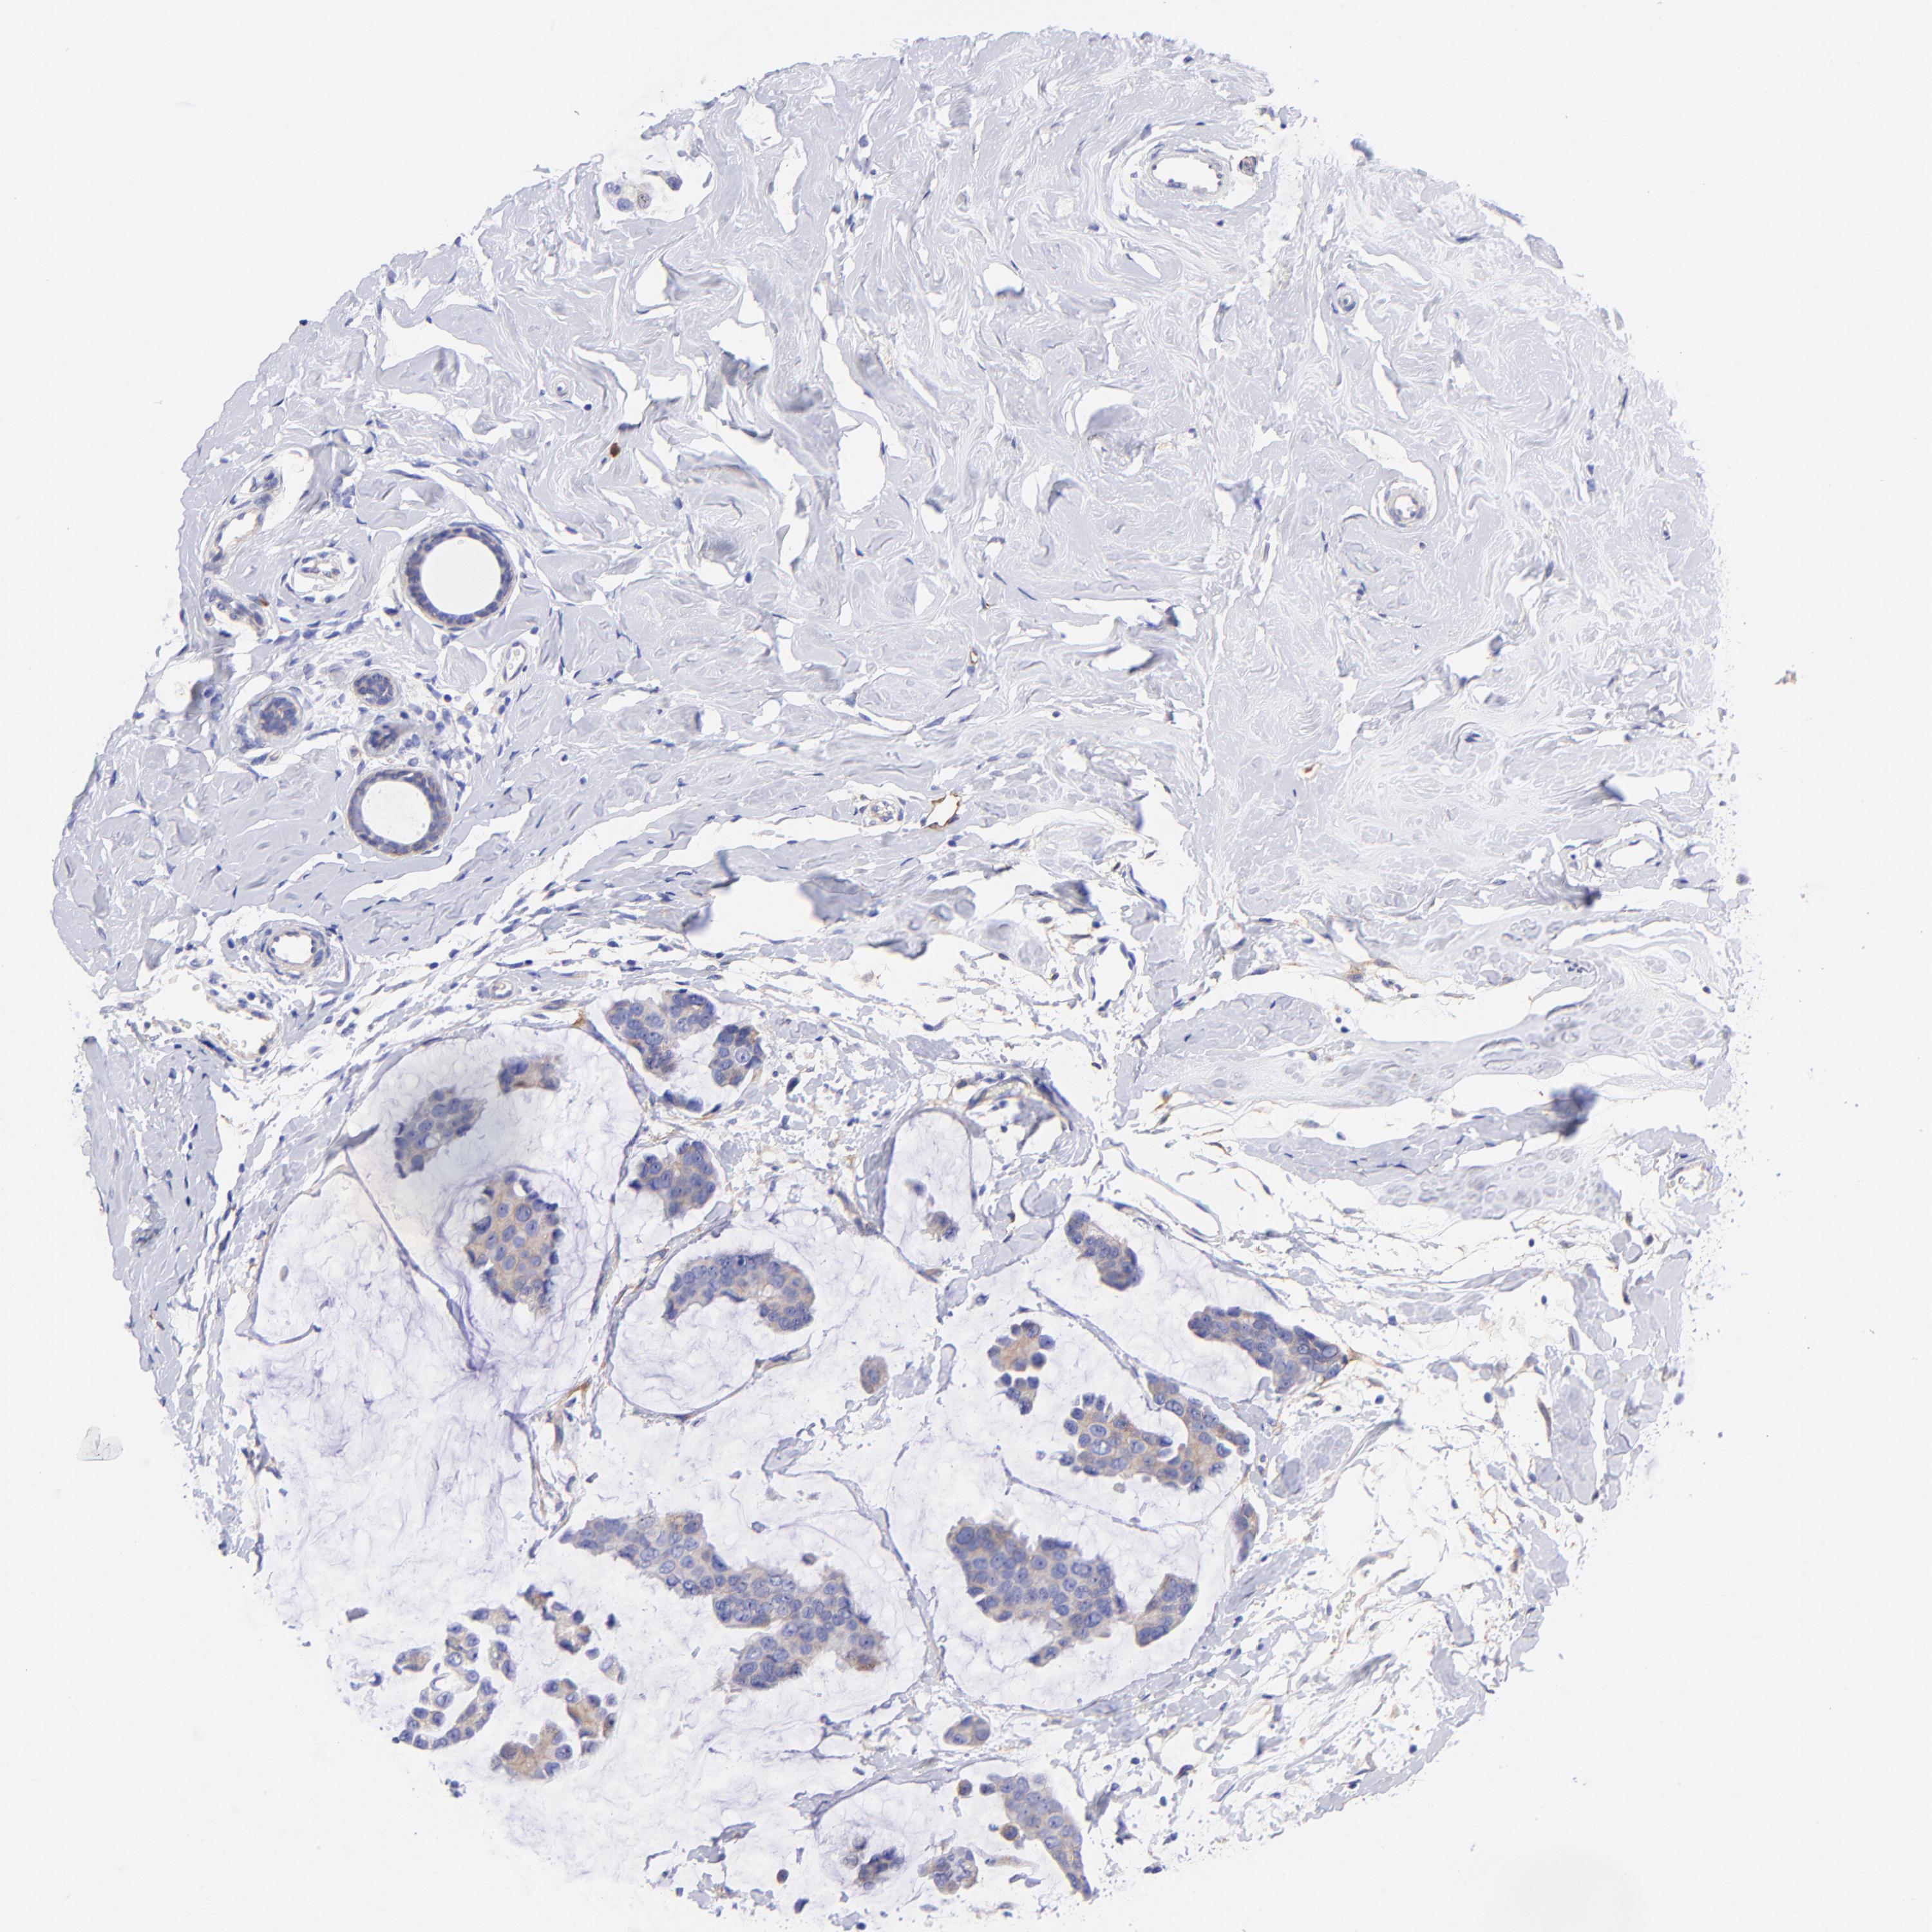

BRCA TCGA BRCA VALIDATION PROTEIN EXPRESSION

ANTIBODIES

AND

VALIDATION